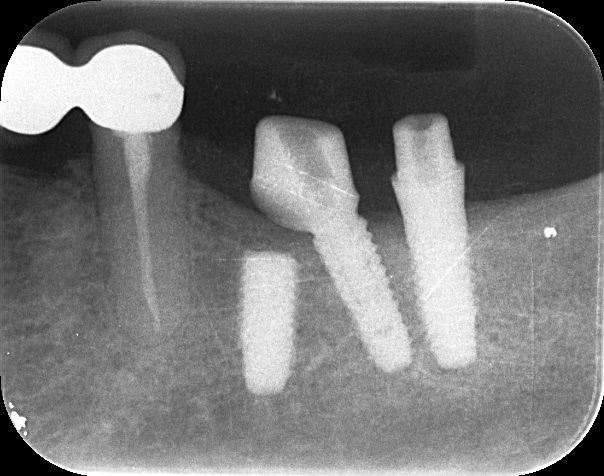

インプラント体にアバットメント(土台)装着

-

ジルコニア修復